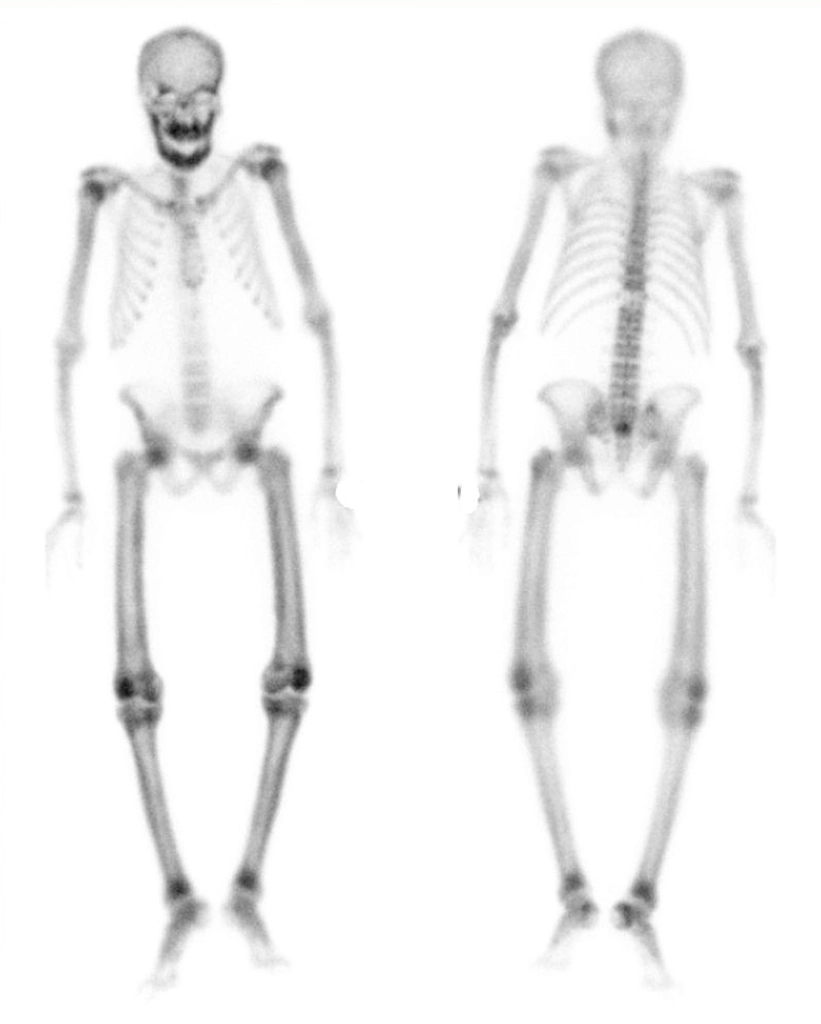

• superscan: generalised increased uptake on Tc-99m pertechnetate bone scan (cf

superior and inferior rib notching